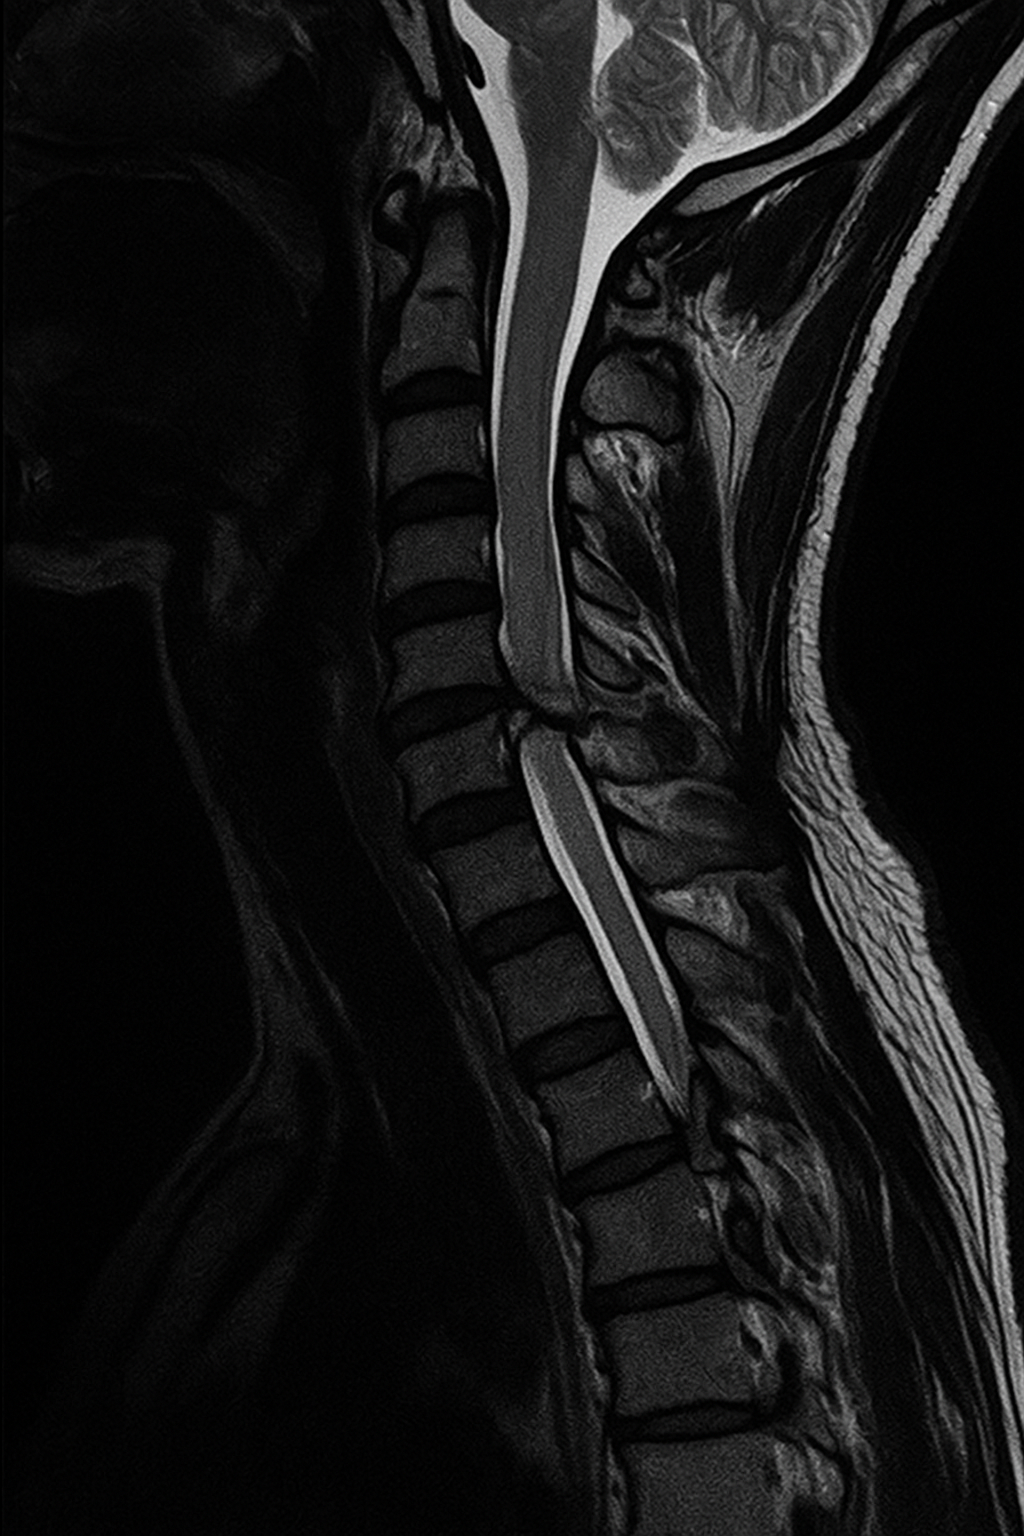

I sällsynta fall kan nacksmärta bero på en mer allvarlig skada, till exempel en fraktur eller kraftig nervpåverkan. En MR-undersökning kan då vara avgörande för att snabbt identifiera skadan och förhindra bestående besvär. Bilden nedan visar ett exempel på en svår skada i halsryggen där MR gjort det möjligt att upptäcka en bruten kota som inte syntes på vanlig röntgen.

Bilden illustrerar en avancerad MR-undersökning av halsryggen där en allvarlig skada på nackens kotor syns tydligt. Vid misstanke om fraktur, kraftig smärta eller domningar i armarna är det viktigt att snabbt söka vård för rätt diagnos och behandling.